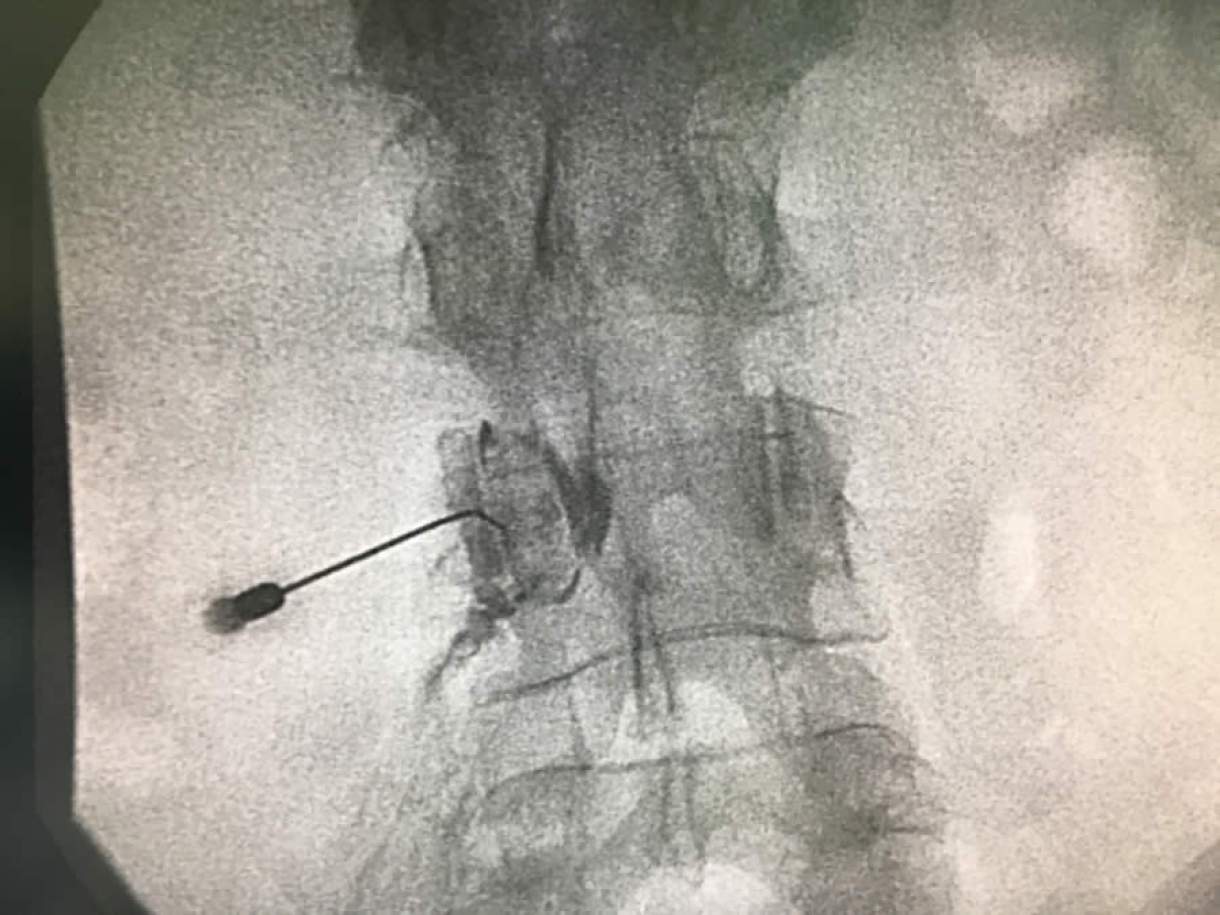

A medicina intervencionista da dor se dedica a diagnosticar e tratar pacientes que sofrem de dor crônica ou aguda. Para isso, são utilizados recursos da radiologia intervencionista e suas técnicas minimamente invasivas (procedimentos guiados por ultrassom, raio-x ou tomografia) para entender a causa da dor e apontar a melhor terapia. “Isso permite a realização de procedimentos sem corte, com menos riscos de infecções e tempo de internação, sempre pensando no bem-estar do paciente”, frisa o especialista. “A maioria dos procedimentos são realizados a nível ambulatorial, ou seja, são realizados com apenas uma sedação leve e o paciente pode ser liberado para casa após algumas horas.”